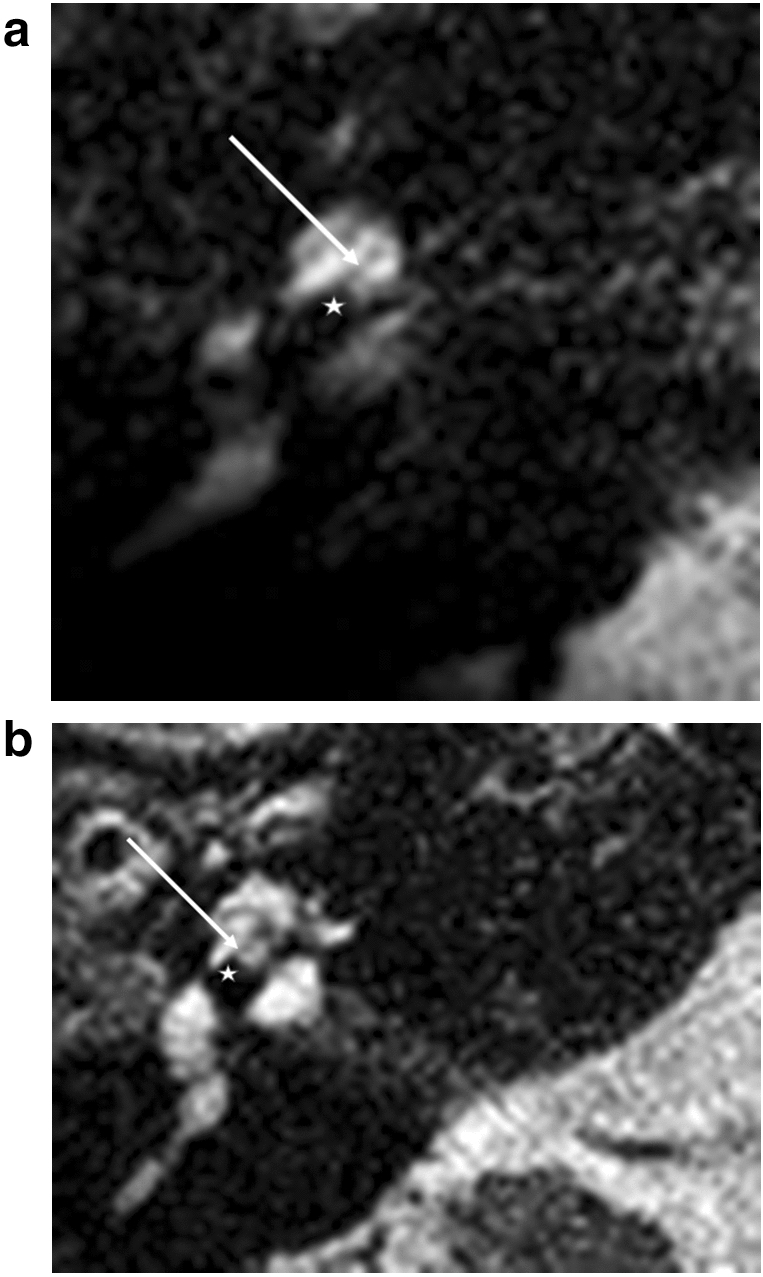

Figure 2.

Straight electrodes, first turn. (a) Flex 28, (b) SlimJ. Star represents diminishing electrode signal, arrow represents basilar membrane.

At the first turn, a design-specific difference of the diminishing signal of the electrodes was obvious. We were able to differentiate between a round signal diminishing and a flatter signal diminishing (Fig. 2a,b). The basilar membrane signal (Fig. 2a,b) and the localization of the fluid signal diminishing indicate scala tympani positions at the first turn for these two types of lateral wall electrodes.